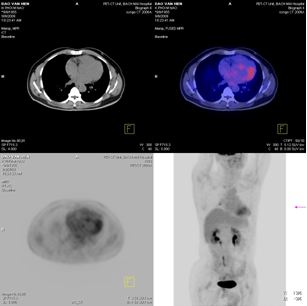

PET/CT

Kết quả: Thành ngực, trung thất và nhu mô phổi 2 bên và các tổ chức ngoài não khác không thấy có hấp thu F-18 FDG bất thường.

· Khối u đã thu nhỏ kích thước (từ 33mm xuống còn 14mm), tổ chức khối u thoái hoá dạng nang (trên PET/CT, max SUV=3,54)

2. Tại phổi

· Khối u tan hoàn toàn

· Không xuất hiện tổn khác tại phổi và ngoài phổi